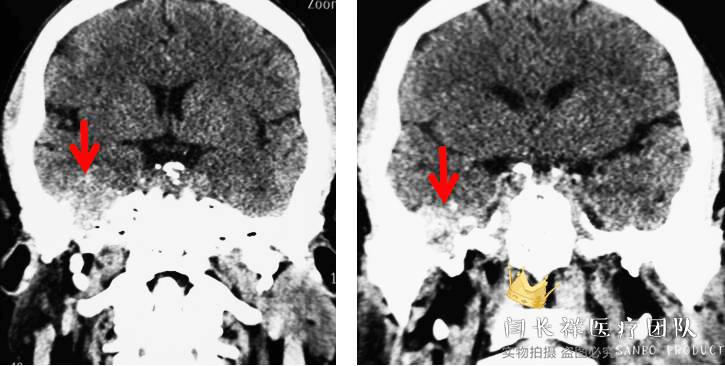

中颅窝-颞下窝占位

术前冠位CT示右侧中颅窝、颞下窝、翼腭窝占位,病灶呈稍高密度。